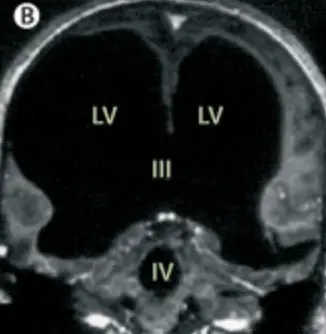

So, when doctors scanned his brain to access the cause of his unexplained leg weakness, they were surprised to find that he had an enormous fluid-filled chamber.

However, this man's brain fluid built up, which left him with a massive deposit of liquid and very little brain matter.

The doctors learned that the man had a condition called Hydrocephalus, a build-up of fluid in the brain; he actually had a shunt placed inside his head at just six years old to drain the fluid, but it was removed when he turned 14.

Speaking about the case, Feuillet confirmed that the fluid buildup had led to a significant reduction in brain matter: "It is hard for me [to say] exactly the percentage of reduction of the brain, since we did not use software to measure its volume. But visually, it is more than a 50 to 75 percent reduction.

"The whole brain was reduced – frontal, parietal, temporal, and occipital lobes – on both left and right sides. These regions control motion, sensibility, language, vision, audition, and emotional and cognitive functions," Feuillet went on to tell New Scientist.